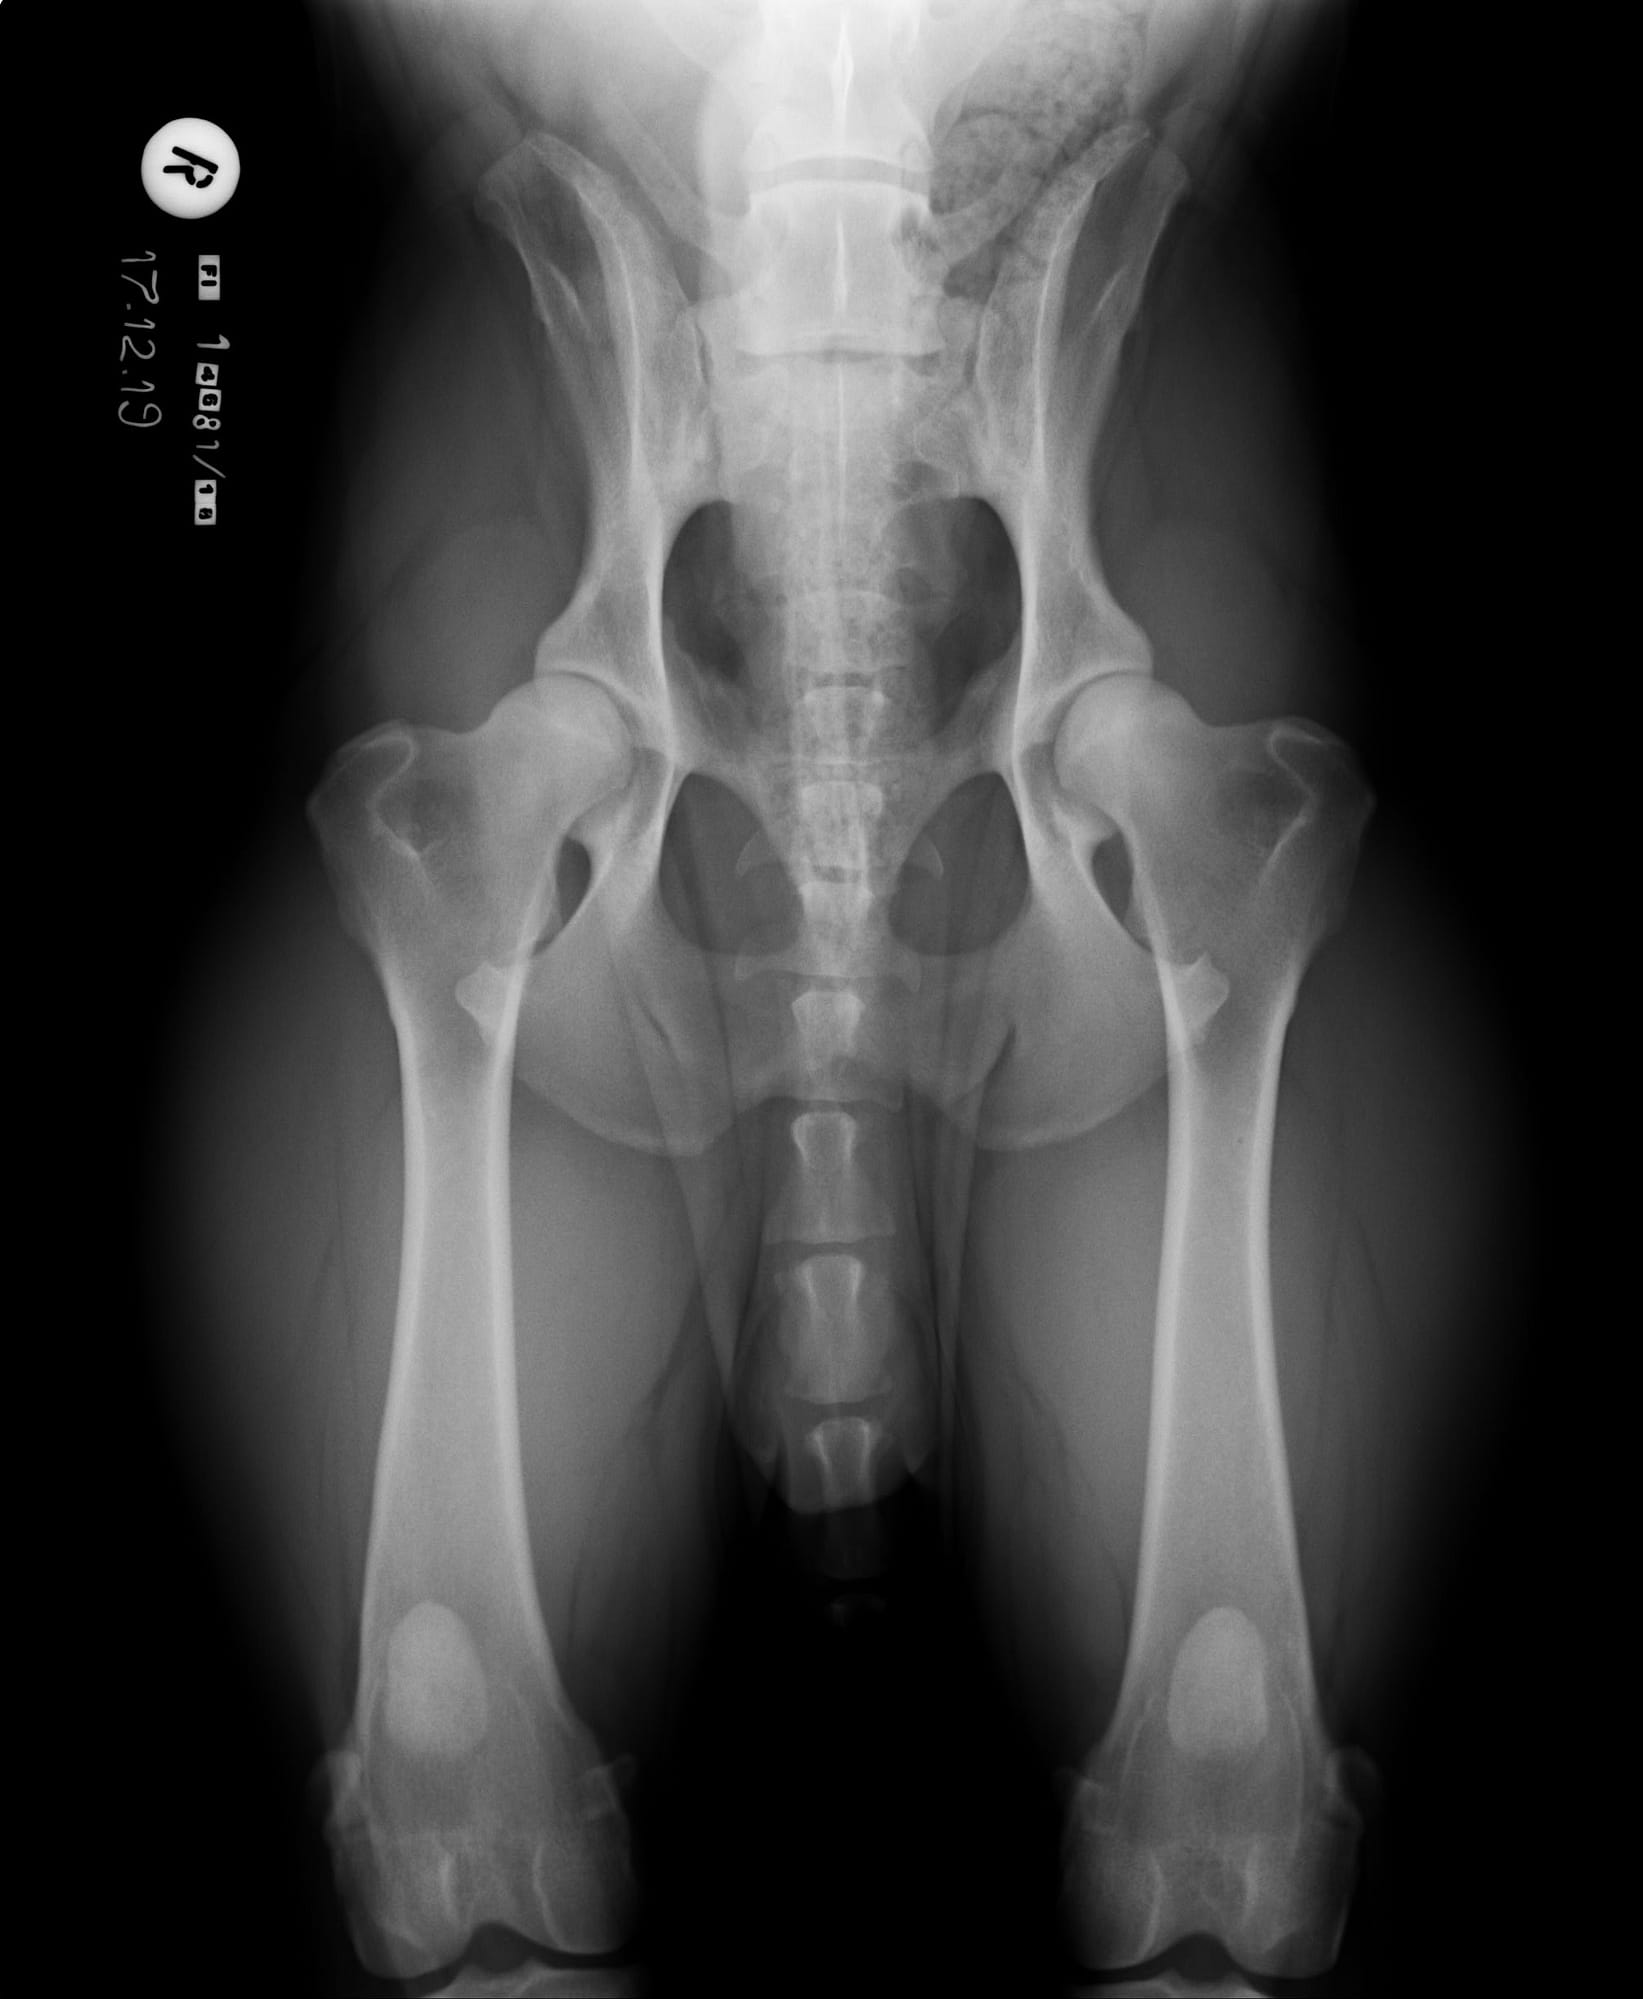

LTV3; asymmetrical; on the right in the VD photo the left side of S1 is shaped like a sacral vertebra and on the right side S1 is shaped like a lumbar vertebra including the spinous process.

The asymmetrical form, LTV3, seems to be a bit more tricky than the other forms. In some cases asymmetrical form comes with rotated pelvis, which might lead to unilateral development in hips. This is actually very logical; when the pelvis is not straight and in balance there will be uneven bear of weight between hips. In long term this uneven state might cause the worse hip wear sooner than the better hip and lameness and osteoarthritis may occur.

In the Finnish Kennel Club’s database 38,9% of Rhodesian Ridgebacks with LTV3 have one hip scored 1-2 degrees lower than the other one, ie. A/C (Oct 2020). The score doesn’t tell if the dog’s pelvis is straight or rotated.

“Asymmetrical LTV favours pelvic rotation over its long axis, resulting in inadequate femoral head coverage by the acetabulum on one side. Inadequate coverage of the femoral head favours subluxation, malformation of the hip joint, and secondary osteoarthritis. Asymmetrical hip conformation may therefore be the sequela of a LTV and mask or aggravate genetically induced canine hip dysplasia.”

(Flückiger M., Frank Steffen F. et al 2017)